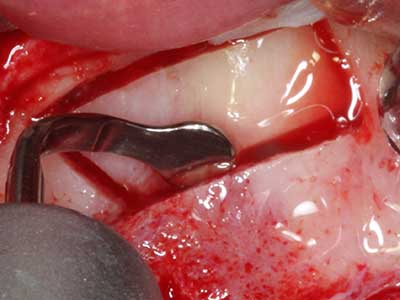

Fig. 3: La separación basal del bloque se ve facilitada con piezas dotadas de una angulación especial.

Fig. 4: Con la rasqueta ósea se obtienen virutas adicionales de hueso autógeno.

En la extracción de bloques óseos la piezocirugía también presenta ventajas adicionales: Además de la alta precisión en la osteotomía que ya se ha descrito antes, se ha comprobado que el uso de los delgados insertos de sierra resulta especialmente cuidadosas con el hueso. Frente a esto, sobre todo cuando se usan las fresas de Lindemann, cabe esperar pérdidas en la extracción significativamente más altas debido al mayor grosor de la parte frontal del cabezal (Lakshmiganthan, Gokulanathan et al. 2012). La separación basal que se necesita en particular en los injertos de bloque extraídos de forma retromolar se ve facilitada mediante sierras perpendiculares especialmente previstas a tal fin, lo que permite considerar que la cirugía piezoeléctrica es un procedimiento preciso y seguro para la obtención de bloques de hueso en el área retromolar (Happe 2007) (fig. 1-12).